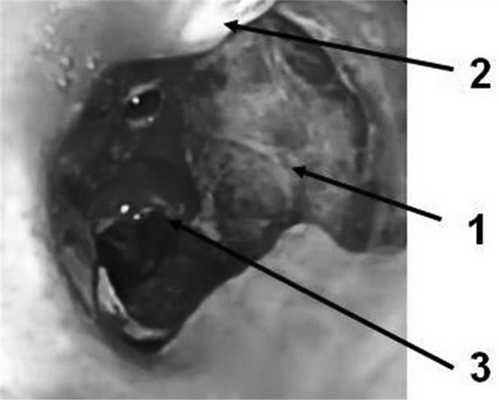

Пациент С., 28 лет, 29.07.14 был придавлен автомобилем к стене. Госпитализирован в ЦРБ г. Александрова, где при обследовании диагностирована тяжелая закрытая травма груди: множественные переломы ребер с двух сторон с разрывом легких, двусторонний пневмоторакс, правосторонний гемоторакс, подкожная эмфизема грудной клетки. Произведены правосторонняя торакотомия, ушивание разрывов верхней доли легкого, санация и дренирование правой плевральной полости, дренирование левой плевральной полости, диагностическая лапаротомия, ревизия органов брюшной полости. Через сутки (30.07.14) для дальнейшего лечения пациент переведен в НИИ СП им. Н.В. Склифосовского. При поступлении состояние больного тяжелое. Сознание - 10 баллов по шкале комы Глазго. Кожные покровы бледные, цианотичные. Искусственная вентиляция легких (ИВЛ) через оротрахеальную интубационную трубку. Грудная клетка равномерно участвовала в акте дыхания. Диагностирована двусторонняя подкожная эмфизема грудной клетки и шеи. Аускультативно дыхание жесткое, ослаблено с обеих сторон, больше справа. По дренажам из правой плевральной полости отмечено периодическое поступление воздуха. ЧСС 124 в минуту, АД 120/70 мм рт.ст. При рентгенологическом исследовании выявлена эмфизема мягких тканей грудной клетки с обеих сторон, переломы II-VII ребер справа и IV-VIII - слева, снижение прозрачности легочного поля в верхних и средних отделах правого легкого за счет контузионных изменений и кровоизлияний. При КТ-исследовании визуализированы множественные полисегментарные ушибы обоих легких с формированием гемопневматоцеле в нижней доле правого легкого, пневмомедиастинум, множественные переломы ребер и эмфизема мягких тканей передней грудной стенки. При фибробронхоскопии (ФБС) через интубационную трубку в просвете трахеобронхиального дерева, больше справа, выявлено значительное количество крови и сгустков. Выполнена санация просвета трахеи и бронхов раствором диоксидина 0,01% 60 мл. Сгустки крови удалены. В промежуточном бронхе визуализирован сгусток крови длиной 20-25 мм, занимающий 2/3 просвета бронха. По латеральной стенке бронха, не прикрытой сгустком крови, определялся дефект стенки бронха. При проведении аппарата дистальнее сгустка визуализировали среднедолевой и нижнедолевой бронхи. При ФБС, выполненной через 12 ч, в просвете бронхов определяли умеренное количество слизистого секрета с примесью крови. На 5 мм дистальнее карины по заднемедиальной стенке правого главного бронха выявлен дефект стенки 10 мм в диаметре с рваными краями и с образованием полости диаметром 10-15 мм (рис. 1). Правый верхнедолевой бронх не изменен, сегментарные бронхи проходимы. На расстоянии 10 мм от шпоры правого верхнедолевого бронха и на уровне верхнего края устья среднедолевого бронха визуализирован циркулярный разрыв стенки промежуточного бронха с диастазом краев 20-25 мм (рис. 2). Средне- и нижнедолевые бронхи правого легкого не изменены. Таким образом, локализация разрывов бронхов не позволяла исключить правостороннюю пневмонэктомию как возможный объем операции. Однако вмешательство с раздельной интубацией бронхов и выключением правого легкого на фоне массивной контузии левого легкого, выраженной легочной недостаточности и постгипоксического синдрома представлялось крайне рискованным. В связи с полным расправлением легких, отсутствием значительного сброса воздуха по дренажам из плевральной полости и нарастающей эмфиземой на фоне ИВЛ решено воздержаться от операции и выбрать консервативную тактику. Проводили комплексную интенсивную терапию: ежедневные двукратные санационные ФБС; антибиотикопрофилактика (цилапенем 4000 мг/сут в/в, метронидазол 1000 мг/сут в/в); переливание иммуноглобулина 100 мл в/в, 2 доз эритроцитной массы и 11 доз свежезамороженной плазмы крови, 100 мл/сут 10% альбумина; муколитическая, ингаляционная, противовоспалительная терапия. На 2-е сутки наложена трахеостома для продленной ИВЛ.

Рис. 2. Циркулярный разрыв промежуточного бронха. 1 - проксимальный край диастаза циркулярного разрыва; 2 - диастаз краев циркулярного разрыва; 3 - дистальный край диастаза циркулярного разрыва.